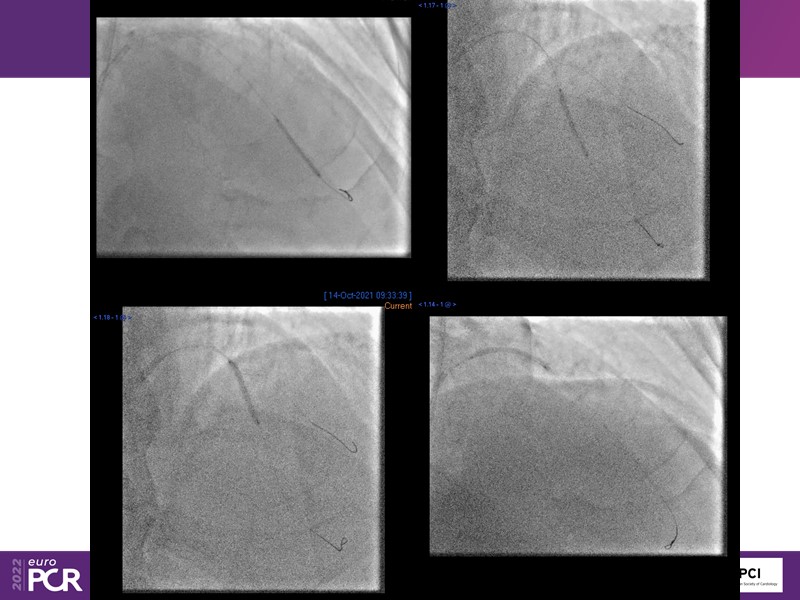

- To find out more about the application and mechanism of a sirolimus coated balloon for coronary artery disease treatment with case presentations in complex settings

- To understand how useful is a DES and DCB stent platform in complex coronary artery disease settings with case demonstrations and follow-up in diabetes mellitus